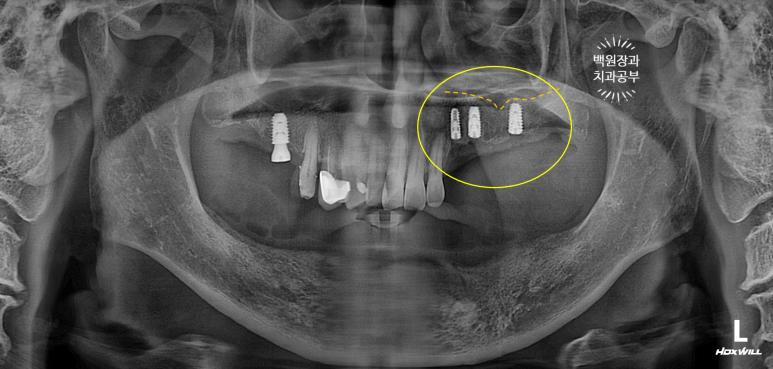

치료가 마무리된 후의 치과용 파노라마 사진입니다.

정~~~말 깔끔하게 마무리가 잘 되었네요!!!

치료 전 후 비교로 가장 명확히 볼 수 있는 사진이 치과용 파노라마 사진입니다.

엑스레이에서 보이진 않지만, 아래턱 전체틀니는 이제 사용하지 않아도 되시게 되었고,

만성 치주염으로 흔들리던 위턱의 임플란트들도 깔끔하게 임플란트로 대체되었습니다.